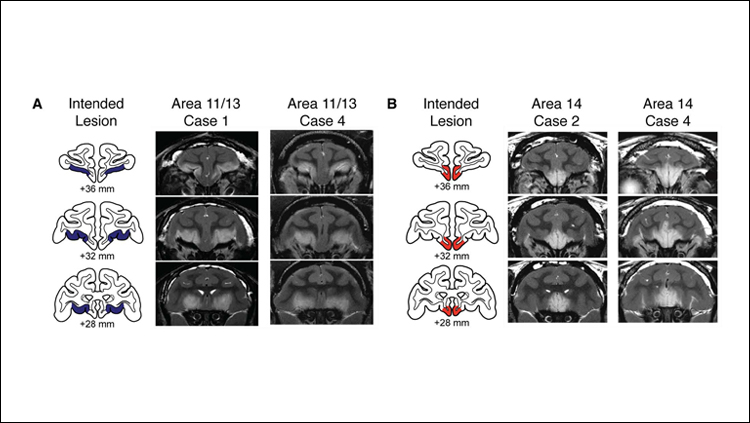

Mar 26, 2019Press ReleaseDamage to parts of the orbitofrontal cortex (OFC), a region within the prefrontal cortex, heightens monkeys' defensive responses to threat, according to new research published in JNeurosci.